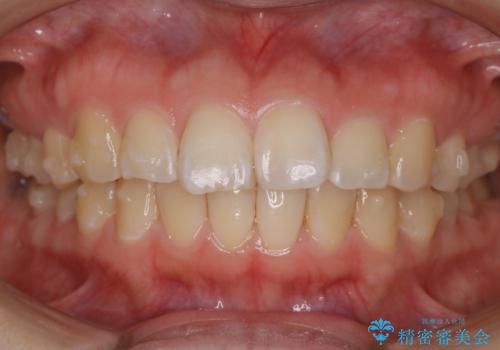

【非抜歯】ガタつきと歯軸を正して長持ちする歯へ

- 歯のガタつきと噛み合わせの改善を主訴に来院されました。

非抜歯で、少量の奥歯の移動と歯列の拡大・IPRを駆使して主訴を改善するための治療計画を立案しました。